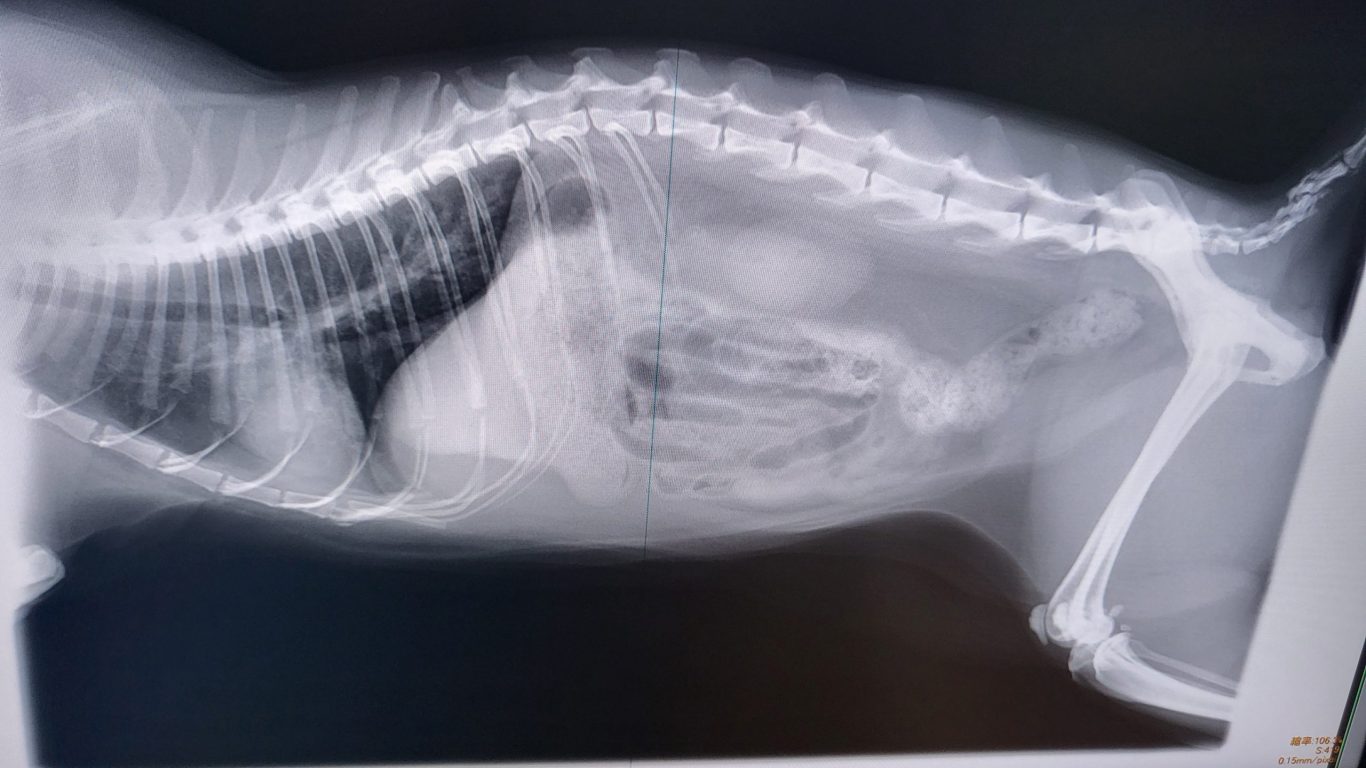

診察室でレントゲンを観ながら先生の診断結果を恐る恐る

写真の後ろ足の骨近くに5センチくらいの「うんち」が映っている

真ん中の腸には空気がつまってるとの事

結果

便秘 ガスだまり だそうな・・・